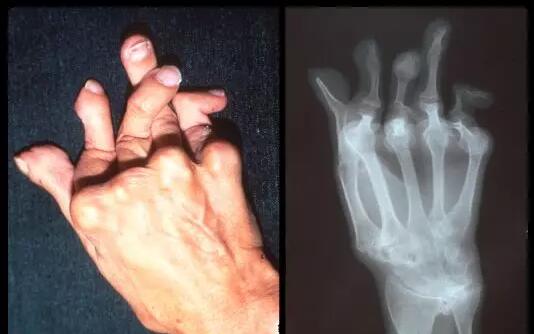

风湿病是因为机体免疫功能紊乱而导致的全身性疾病,可损及关节、肌肉、内脏等多个靶器官,关节是最常见也是受累最多的部位,由于多样复杂的发病因素和受治疗技术、治疗条件的限制,大多数患者因为没有条件接受系统、规范的治疗,病情得不到有效控制而最终导致身体残疾。据国家卫健委统计,目前我国风湿病患者数量约为2.5亿人,重症患者有8000万人,其中约有53%的患者因疾病导致肢体残疾,因此风湿病被医学界称之为“世界头号致残疾病”。

类风湿导致手指残疾